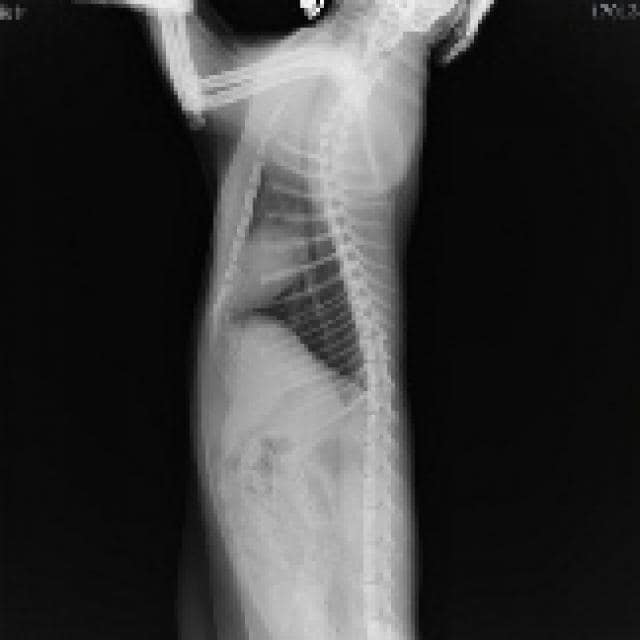

Chest X-rays would also be included because they are a relatively inexpensive and easy way to get a peek at the heart and lungs. X-rays have some limitations, however. Radiographic images do a good job of revealing the overall shape of the heart (i.e., too big or with an abnormal bulge in a particular area). Where they come up short, though, is at looking inside the heart and assessing heart function. An electrocardiogram (EKG) can help fill in some of these gaps.

Seeing changes in the appearance of the lungs on an X-ray can be very useful. Certain patterns and their locations often correspond to particular diseases. For example, an alveolar pattern in the dorsal (i.e., upper) lung fields is typically seen with left-sided heart failure, while a similar pattern located lower down in the lungs often develops with bronchopneumonia or aspiration pneumonia.

Image: Leica’s X-Ray by 今 ゆっくりと 歩いていこう / via Flickr